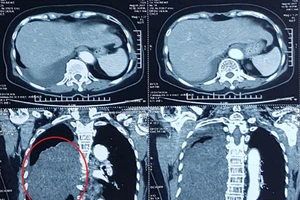

Cắt bỏ khối u ‘khủng’ chèn lệch tim bệnh nhân